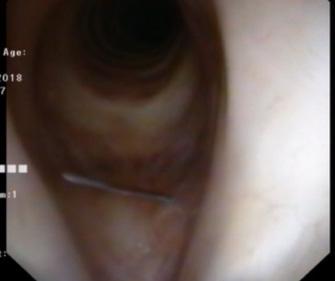

Anestezia locală

Pentru procedurile in-office, anestezia locală este esențială pentru confortul și cooperarea pacientului și succesul intervenției.

Tehnici uzuale (adaptate la practica autorului):

• Instilație nazală de lidocaină 4% și metazolină;

• Spray oral de lidocaină 10%;

• Instilație laringiană de lidocaină 4%, fie transoral cu o canulă de instilație sub control fibroscopic (Fig. 1), fie prin ca-

nulă endoscopică prin canalul de lucru (în opinia autorului, mai eficientă și mai ușor tolerabilă);